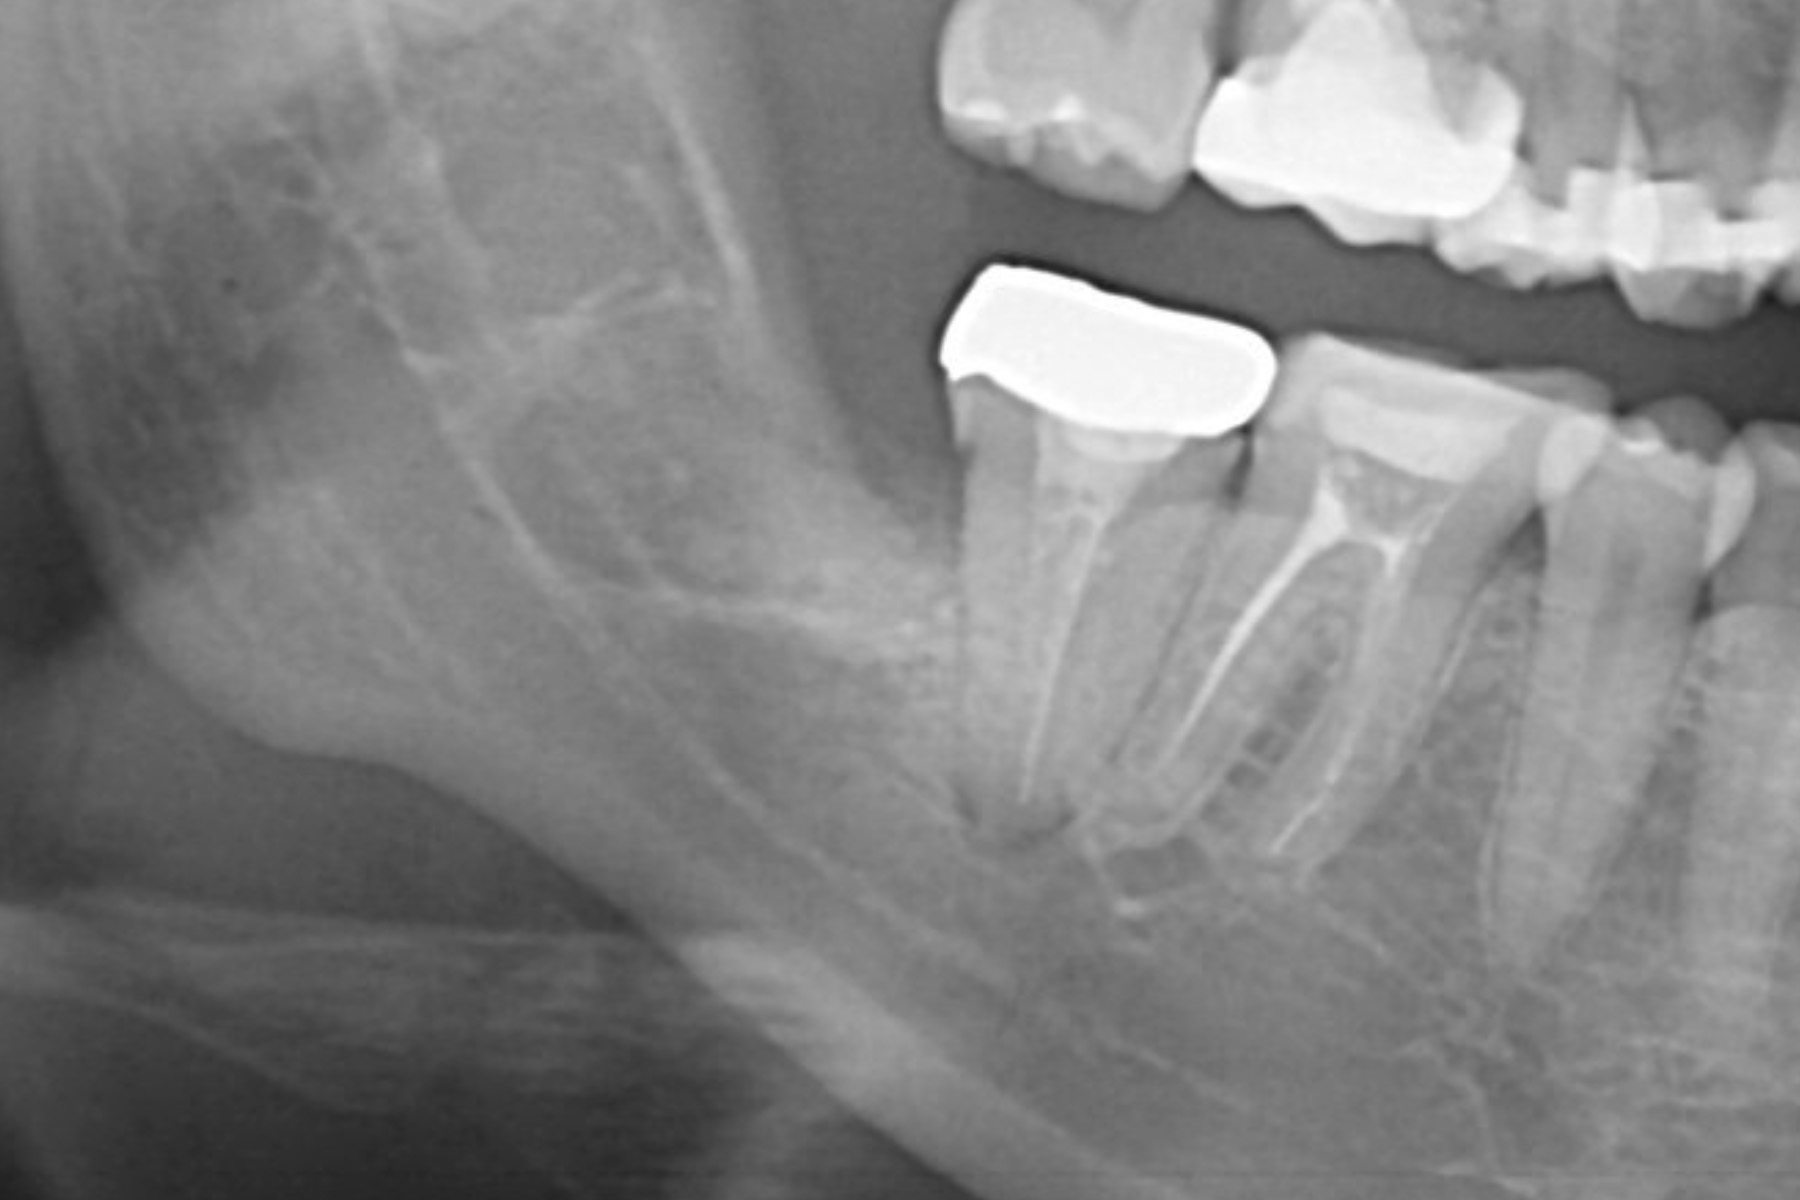

wisdom-case01-af